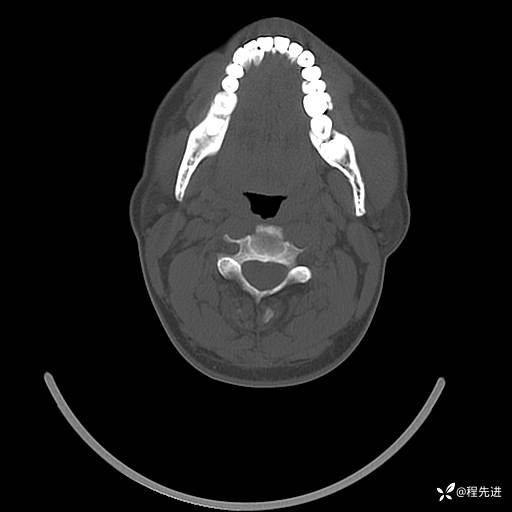

CT平扫+增强: